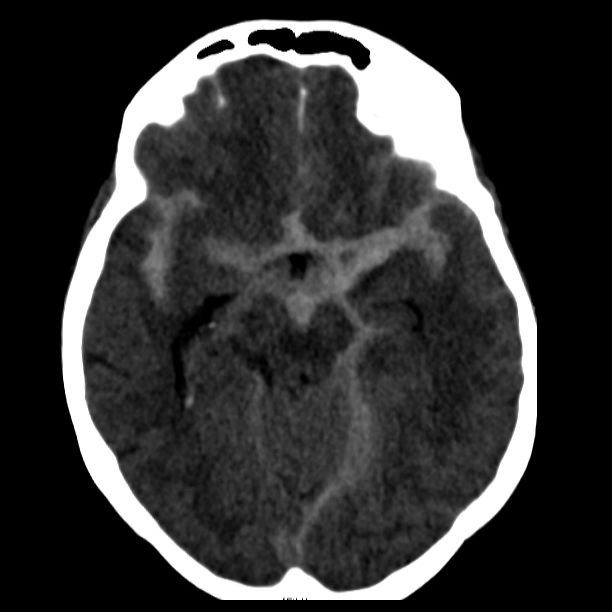

Als schnellste und sicherste Maßnahme gilt das craniale Computertomogramm (CCT). Hier lässt sich eine frische SAB meist zuverlässig darstellen, wobei auch bereits richtungsweisende Befunde, wie das Ausmaß der Blutung und eine eventuelle Lokalisation eines möglichen Aneurysmas bestimmt werden können. Darüber hinaus kann ein Angio-CCT, bei dem zusätzlich Kontrastmittel verabreicht wird und dann die intrazerebralen Blutgefäße gesondert rekonstruiert und dargestellt werden, weitere Informationen liefern. Der sogenannte “Goldstandard” zur Diagnose zerebraler Gefäßmissbildungen ist jedoch die zerebrale Angiographie. Dabei wird mit Hilfe eines speziellen Katheters über die Leisten- oder Armarterie Kontrastmittel gegeben und die zerebralen Blutgefäße hoch selektiv dargestellt. Sollten sich auf dem initialen CCT Zeichen des Hirnwasseraufstaus zeigen, der durch ein Verstopfen der Abflusskanäle durch das neu aufgetretene Blut bedingt ist, ist oft die Anlage einer Hirnwasserableitung nach außen notwendig (externe Ventrikeldrainage).

CT Bildgebung der klassischen subarachnoidalen Blutverteilung nach SAB